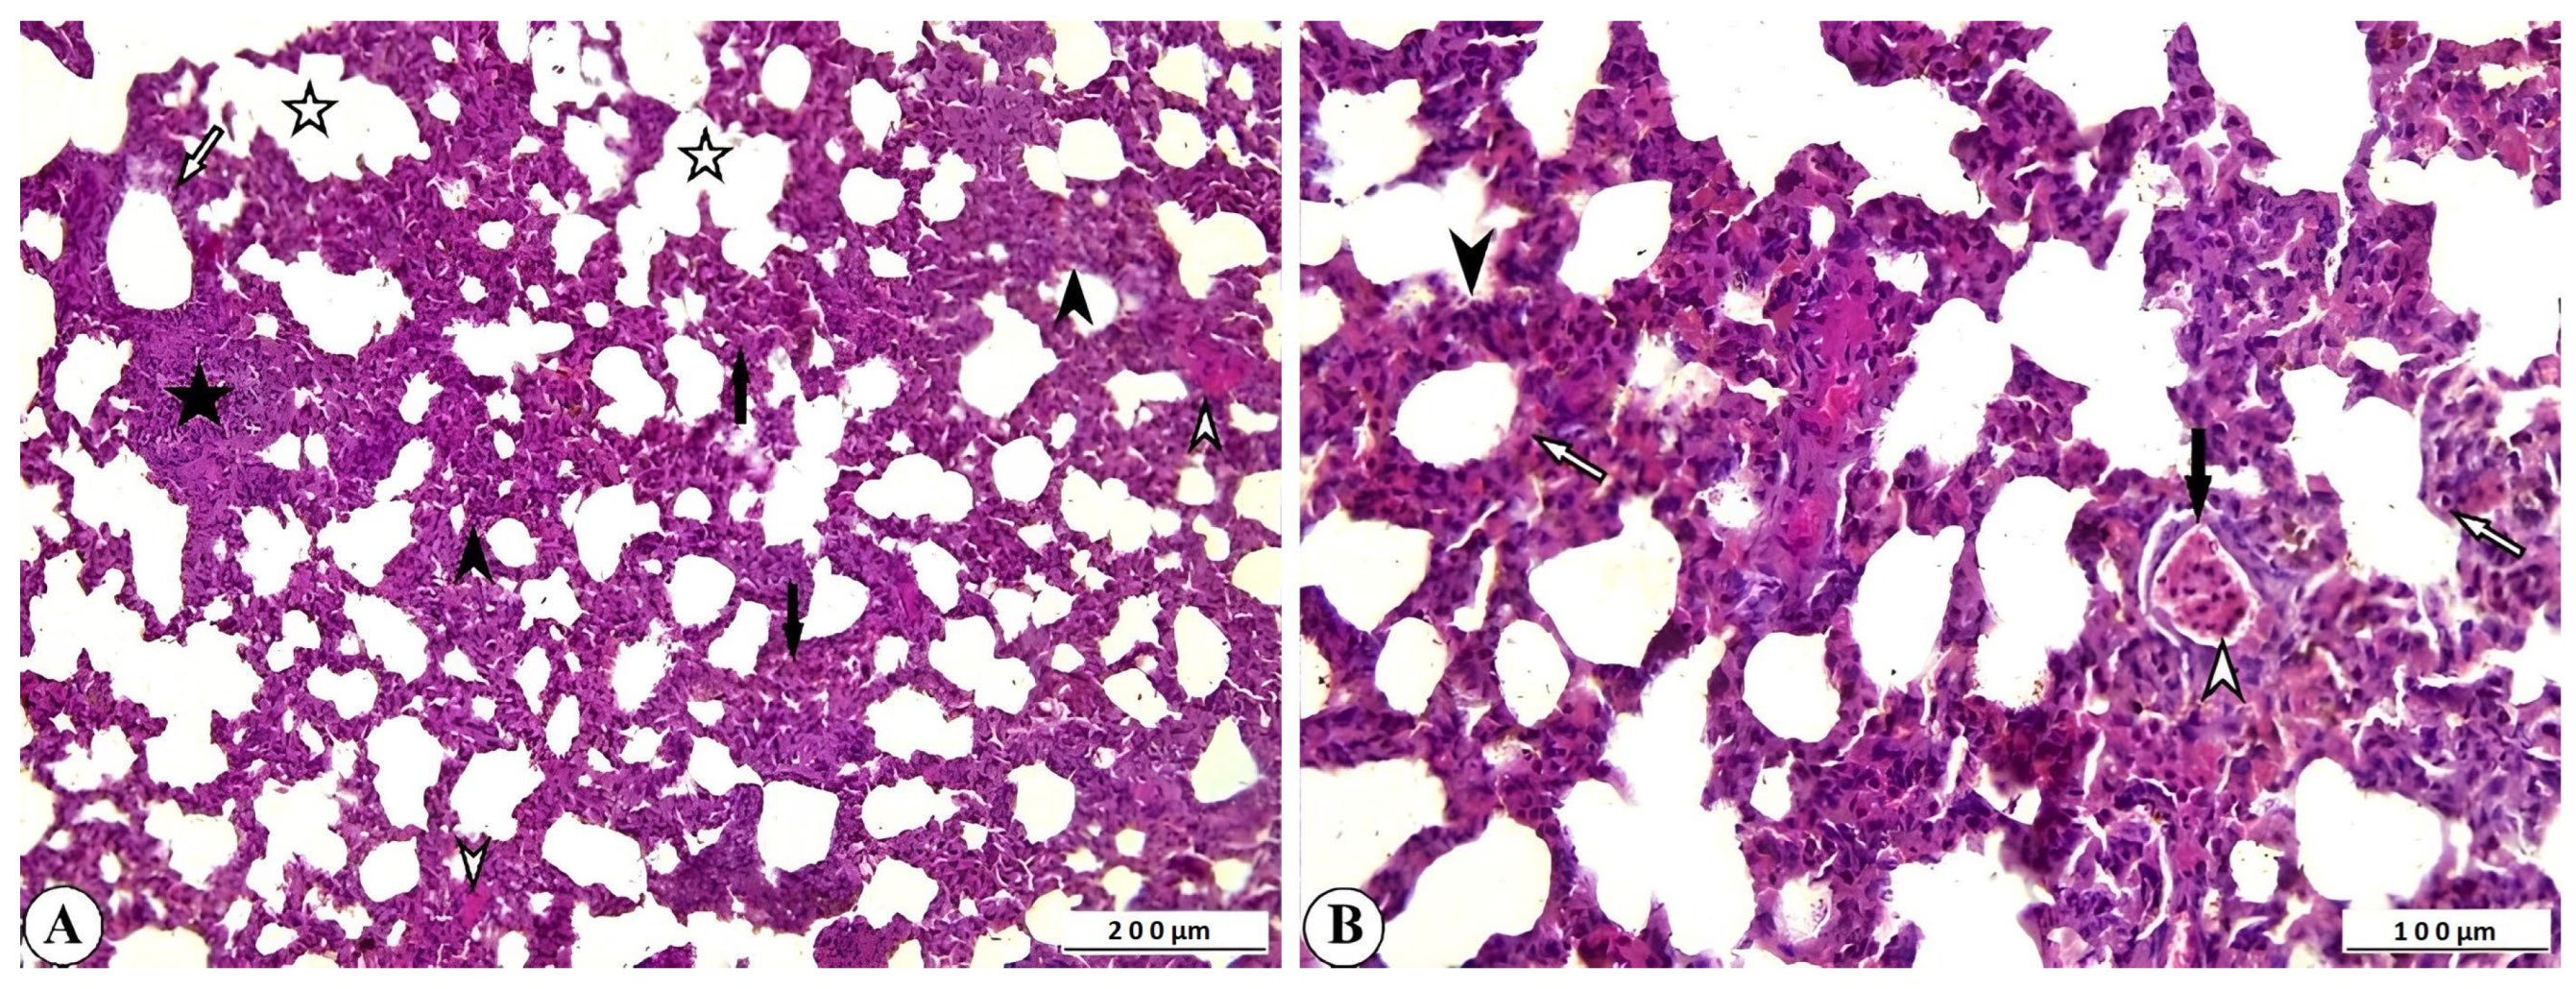

Histopathological examination of lung tissue from rotavirus-infected calves generally revealed a pattern with interstitial pneumonia. One of the most notable findings was the thickening of the interalveolar septa due to proliferative changes and inflammatory cell infiltration. Inflammatory cell infiltration was also present within the interstitium, as well as in the vessels and their surrounding areas. Mild exudative changes associated with hyperemia were observed in the interstitial regions where proliferative inflammation predominated. Inflammation and associated exudation were nearly absent from the lumens of the bronchi, bronchioles, and alveoli; however, degenerative and necrotic lesions were noted within the bronchioles and alveoli. Mild fibromuscular hypertrophy was detected around the bronchioles and alveolar ducts, and lymphoid hyperplasia was observed in the peribronchial and peribronchiolar regions, and to a lesser extent around the alveoli. While atelectasis developed in some alveoli, extensive emphysematous areas resulting from rupture were observed in others following compensatory expansion (Figure 3A,B).

Figure 3. (A) Inflammatory cell infiltration and interalveolar thickening due to proliferation (arrowheads), peribronchiolar lymphoid hyperplasia (star), fibromuscular hypertrophy (open arrowheads), degenerative-necrotic changes in bronchiolar epithelium (open arrow), alveolar emphysema (open stars), and atelectasis (arrows) in cattle lung, ×100, Bar: 200 µm, HE. (B) Interalveolar thickening (arrowhead), degenerative-necrotic changes in bronchiolar epithelium (open arrow), inflammatory cell infiltration (open arrowhead), hyperemia (arrow) in cattle lung, ×200, Bar: 100 µm, HE.